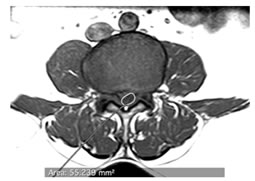

CASE 2

T1 AND T2 W AXIAL IMAGES SHOWING DIFFUSE DISC BULGE WITH SEVERE BILATERAL FACETAL ARTHROPATHY AND LIGAMENTA FLAVA THICKENING AT L5-S1 LEVEL CAUSING MODERATE THECAL SAC STENOSIS, NARROWING OF LATERAL RECESS WITH COMPRESSION OVER BILATERAL TRAVERSING NERVE ROOTS. AN INTRASPINAL SYNOVIAL CYST IS ALSO SEEN ARISING FROM FACET JOINT ON THE RIGHT.

AXIAL T1 AND T2 W IMAGES SHOWING HYPOINTENSE SIGNAL ON PEDICLE OF S1 VERTEBRA ON LEFT SIDE SUGGESTIVE OF SCLEROTIC LESION POSSIBLY OSTEOMA